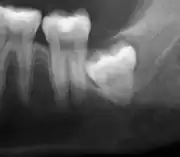

Impacted wisdom teeth are classified by their direction of impaction, their depth compared to the biting surface of adjacent teeth and the amount of the tooth's crown that extends through gum tissue or bone. Impacted wisdom teeth can also be classified by the presence or absence of symptoms and disease. Screening for the presence of wisdom teeth often begins in late adolescence when a partially developed tooth may become impacted. Screening commonly includes a clinical examination as well as x-rays such as panoramic radiographs.

Impacted wisdom teeth are classified by the direction and depth of impaction, the amount of available space for tooth eruption, and the amount of soft tissue or bone (or both) that covers them. The classification structure helps clinicians estimate the risks for impaction, infections and complications associated with wisdom teeth removal.[6] Wisdom teeth are also classified by the presence (or absence) of symptoms and disease.[7]

Impacted wisdom teeth are often described by the direction of their impaction (forward tilting, or mesioangular being the most common), the depth of impaction and the age of the patient as well as other factors such as pre-existing infection or the presence of pathology (cysts, tumors or other disease).[5]: 143–144 Each of these factors is used to predict the difficulty (and rate of complications) when removing an impacted tooth, with age being the most reliable predictor[8] rather than the orientation of the impaction.[9]